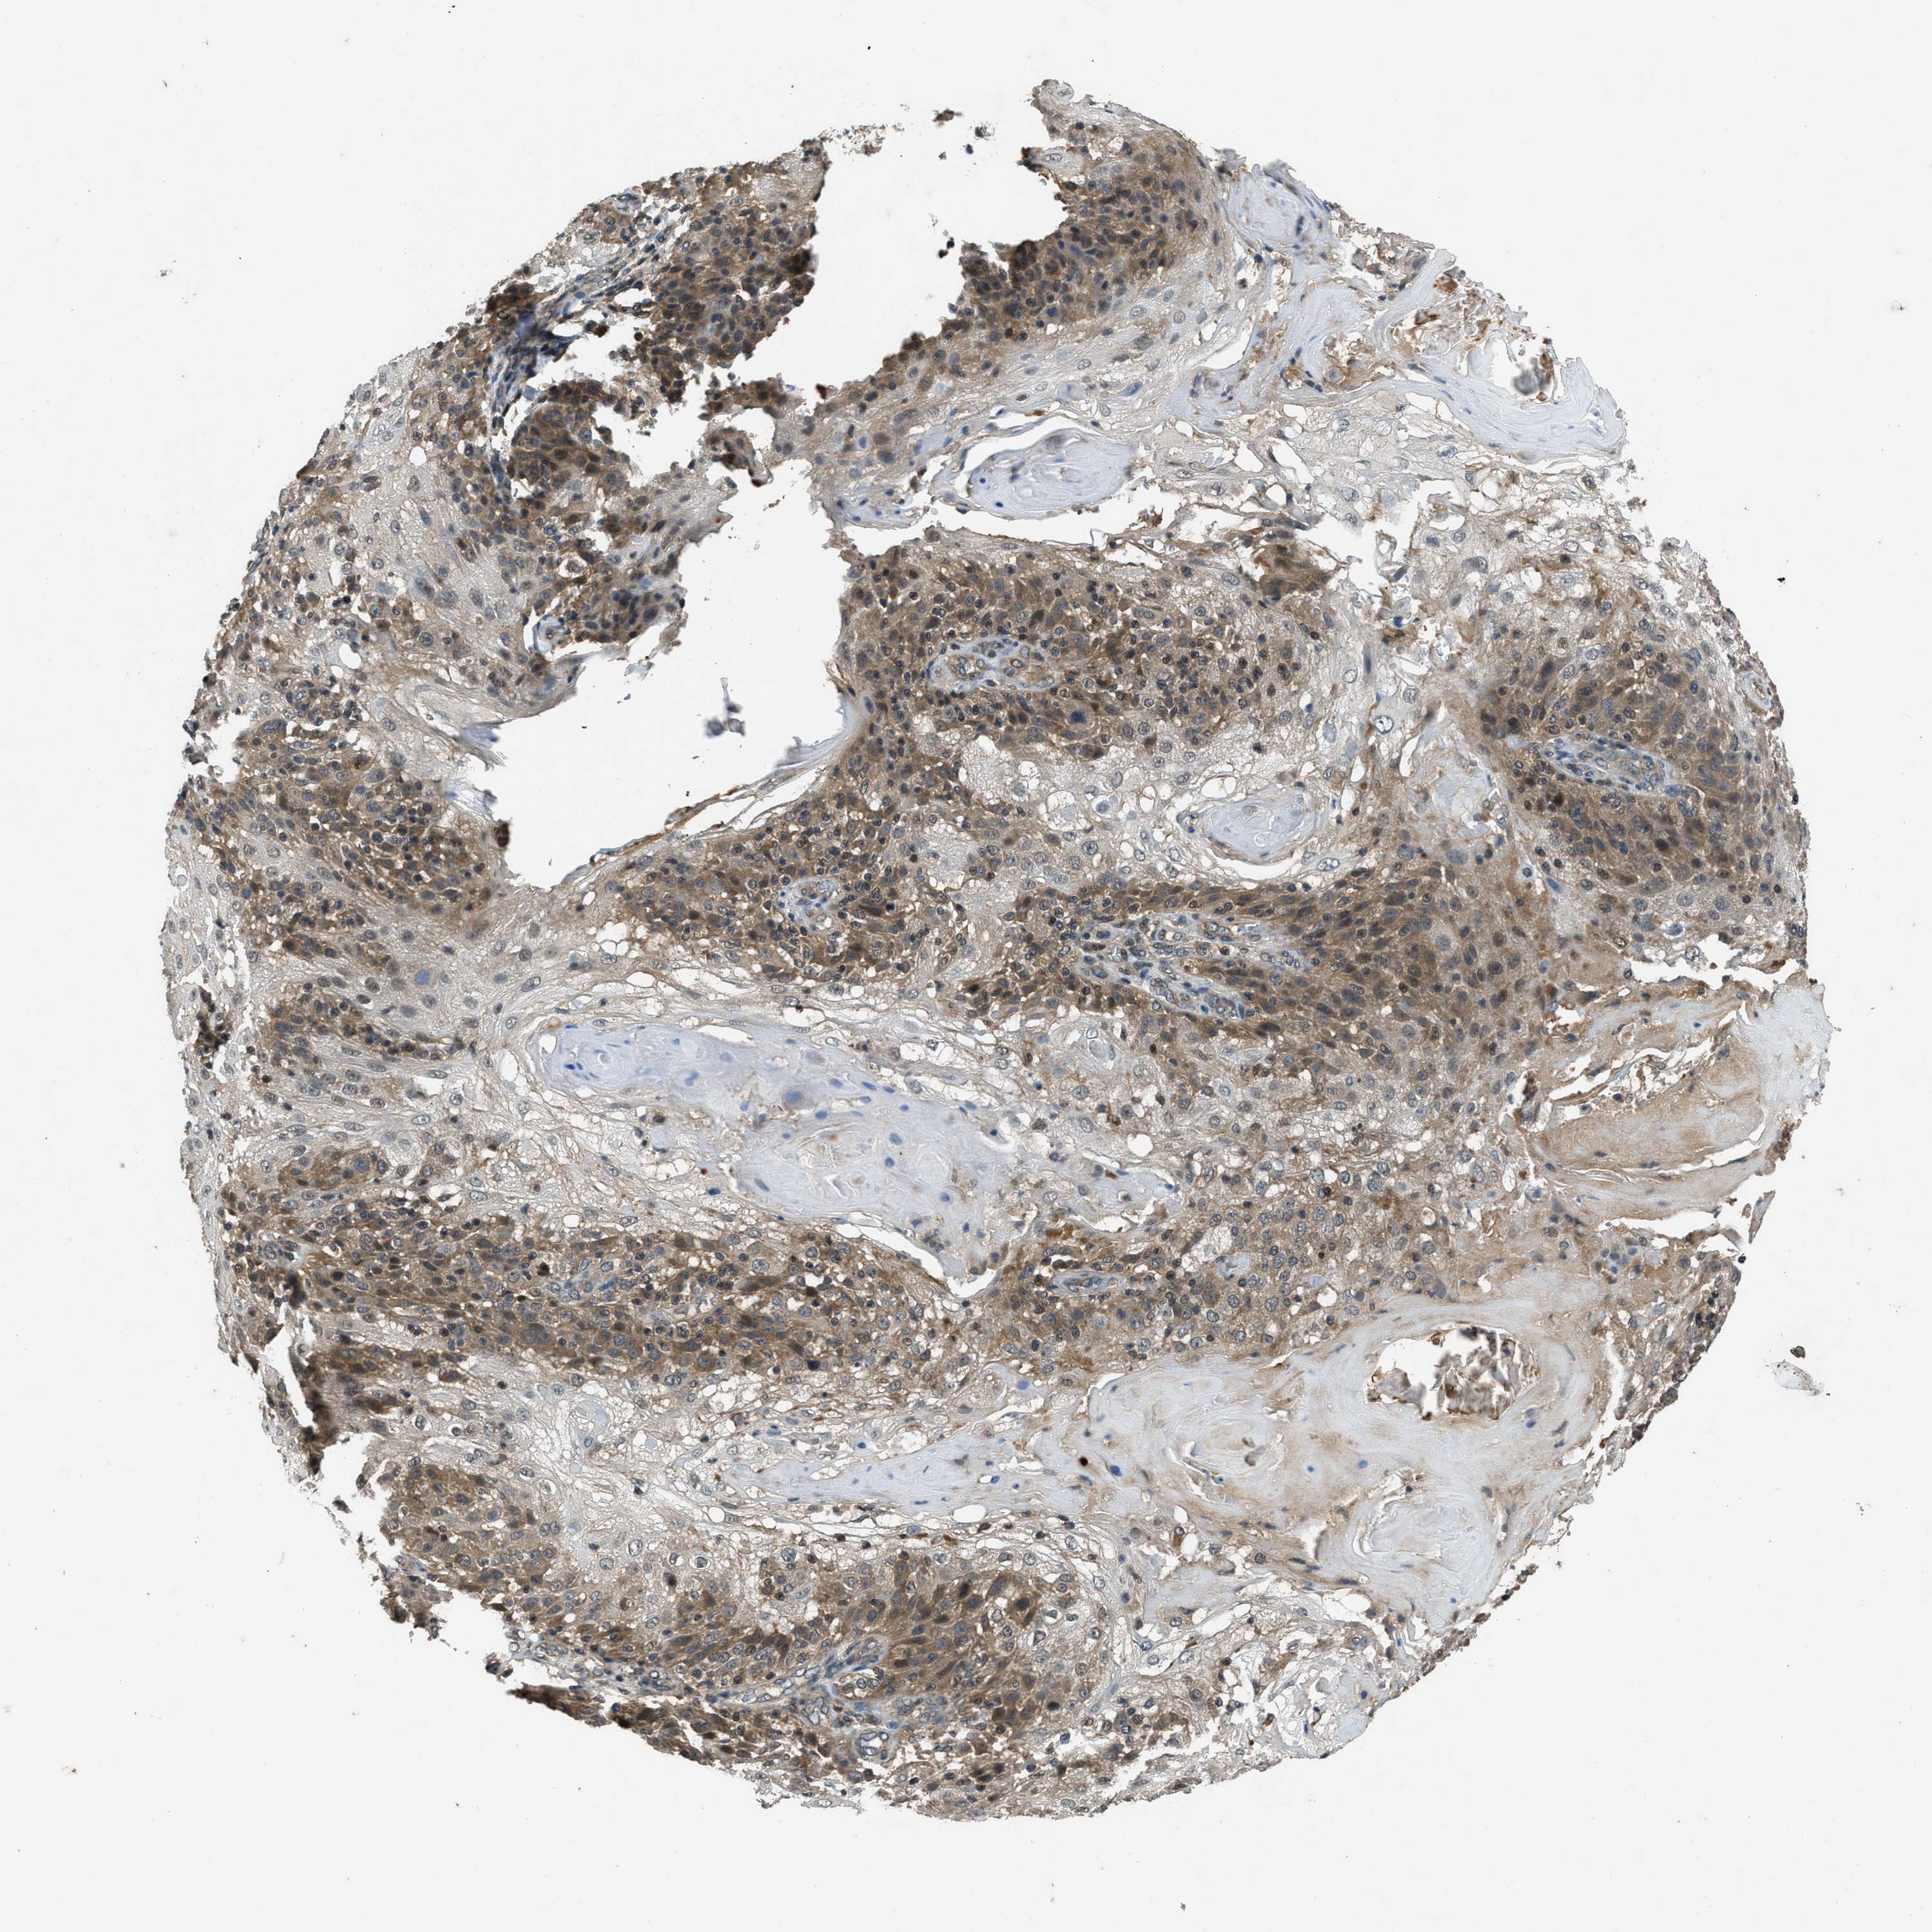

SKIN CANCER - Protein expressioni

A mouse-over function shows sample information and annotation data. Click on an image to view it in a full screen mode. Samples can be filtered based on level of antibody staining by selecting one or several of the following categories: high, medium, low and not detected. The assay and annotation is described here.

Each image is clickable and will lead to virtual microscopy that enables deeper exploration of all samples and also displays staining intensity scores, fraction scores and subcellular localization as well as patient and tissue information for each sample.

Antibody CAB017566

Staining

High

Intensity

Strong

Quantity

>75%

Location

Nuclear

Squamous cell carcinoma, NOS